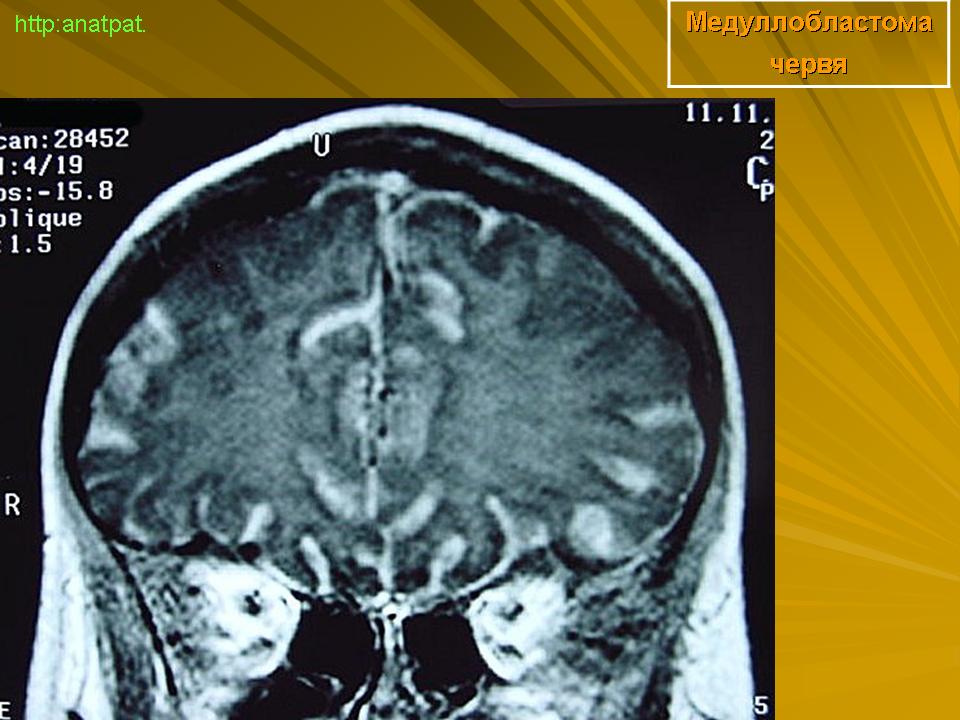

Медуллобластома - это опухоль, которая возникает из примитивных и эмбриональных клеток ЦНС. Локализируется исключительно в мозжечке и представляет 15-20% от детских опухолей мозга. 20% медуллобластом появляется в зрелом возрасте.

Это быстро растущая опухоль, очень злокачественна, имеющая тенденцию распространяться вдоль путей движения ликвора.

Вследствие локализации в мозжечке, обструкция путей циркуляции ликвора является достаточно частой и ранней, с последующей гидроцефалией. Синдром повышенного внутричерепного давления наряду с расстройствами равновесия, являются наиболее частыми и ранними признаками и симптомами.